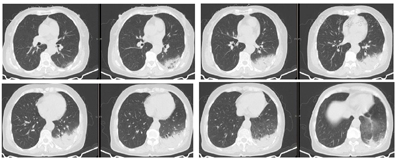

例1,女性,65岁,主因"发热、咳嗽7 d,言语不清、步态不稳、意识障碍1 d"于2021年12月27日入院。患者7 d前无明显诱因出现发热,未测体温,伴畏寒、乏力、头痛、全身肌肉酸痛、干咳,左侧胸痛。自行口服"感冒药"症状未见好转,每日体温波动于36.5~38.0℃,未予诊治。2 d前体温升高达40℃,就诊于发热门诊,鼻咽拭子乙型流感快速抗原检测阳性,血常规示白细胞4.91×109/L,中性粒细胞占比0.86。胸部CT示左下肺大片实变影(图1)。诊断为乙型流感,社区获得性肺炎。予莫西沙星400 mg每日1次、帕拉米韦300 mg每日1次抗感染治疗。1 d前患者出现言语不清、共济失调步态、烦躁、谵妄、尿潴留,为求进一步诊治收入我科。患者既往体健,个人史、婚育史、家族史无特殊。入院体格检查:T 39.0℃,P 103次/min,R 20次/min,BP 115/80 mmHg(1 mmHg=0.133 kPa)。左下肺可闻及湿啰音。心腹体格检查未见异常。双下肢无水肿。神经系统体格检查:定向力障碍,双侧瞳孔等大正圆,对光反射灵敏,颈软无抵抗,言语不利,共济失调步态,指鼻试验阳性。四肢肌力V级,肌张力正常。病理征阴性。

患者老年女性,急性起病,流感季节出现发热、咳嗽,流感快速抗原检测结果为乙流阳性,临床可初步诊断为流感。但患者胸部影像表现为左下肺叶段分布的实变影,与典型流感病毒肺炎不符。可进一步行下呼吸道标本如支气管肺泡灌洗液行流感病毒检测以协助诊断。

患者老年患者,急性起病,发热咳嗽,伴明显神经系统症状,胸部影像表现为左肺实变,肝酶升高,肌酶明显升高,低钠血症,需考虑军团菌肺炎,但患者血象不高,PCT不高,尿嗜肺军团菌抗原阴性则不支持军团菌肺炎的诊断。

鹦鹉热的实验室检查缺乏特异性,血常规白细胞通常正常,但分类可有核左移。C反应蛋白、血沉通常明显升高。肝酶轻度升高和低钠血症常见。微量免疫荧光法检测血清鹦鹉热衣原体抗体是常用的诊断手段,血清抗体滴度四倍以上变化,或抗体滴度>16,具有诊断意义,但我国各医院的实验室并不常规开展该检测。鹦鹉热衣原体的培养技术难度高,并且培养时有高度传染性,只能在生物安全级别3级以上的特殊实验室进行。传统病原学诊断技术存在诸多缺陷,基于宏基因组测序的病原检测技术显示出了巨大的应用价值,近年来国内外关于鹦鹉热文献报道几乎都来自于mNGS测序结果[3]。鹦鹉热胸部影像学可以表现为不同程度的实变和渗出,多表现为胸膜下实变影,下肺多见。实变累及范围与病情严重程度相关。胸腔积液少见[1,3,10,11,12]。